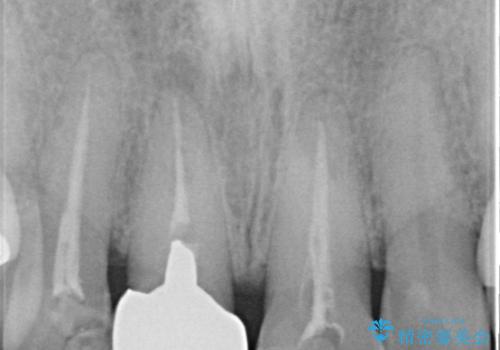

根管治療について

保険根管治療は回数がかかることが多く、終了予定がわかりにくいです。

当院では、根管治療は長い時間のご予約を頂き、多くの場合2~3回で終わります。

根管治療は歯内の治療なので患者様には見えない場所ですが、ここが細菌で汚染されると激しい痛みや長引く違和感の原因になります。

当院では、清潔な治療を徹底し、顕微鏡を使用した精密な治療を行っています。

症状や根管の状態により、治療金額が異なります(5~10万円目安)。治療回数による費用負担の増減はありません。

根管治療専門医をご紹介させて頂く場合がございます。